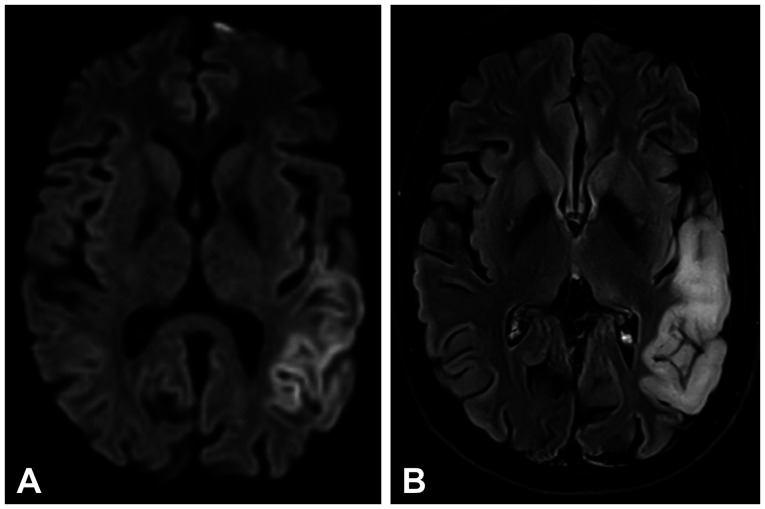

Stroke-Like Episode, Aphasia, and Hearing Loss in MELAS.

MELAS患者卒中样发作、失语和听力损失。